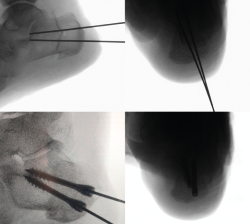

Osteosíntesis

Una vez comprobado el suficiente desplazamiento en la proyección axial del calcáneo, se fija la osteotomía con 2 agujas de Kirschner sobre las que se introducirán 2 tornillos canulados de un tamaño de entre 5,5 y 7 mm, y se verifica su correcta colocación en la visión lateral y axial fluoroscópica (Figura 9).

Figura 9. Imágenes fluoroscópicas de fijación de la osteotomía con agujas de Kirschner y tornillos canulados en anteroposterior y axial del calcáneo.